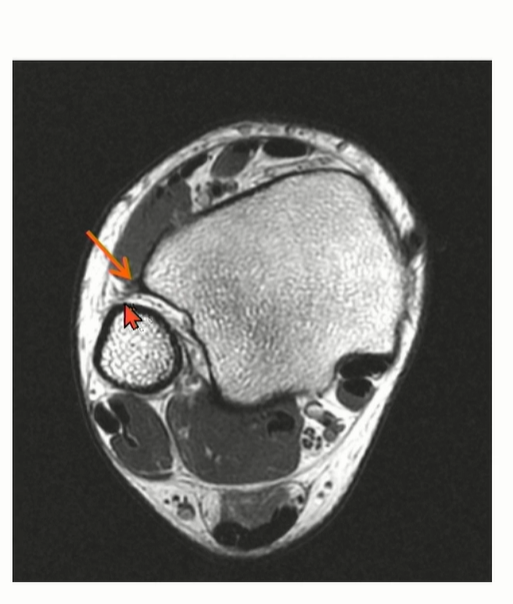

Peroneal tendon을 landmark로 이용해서 CFL를 찾는 것도 연습해야 함.

Axial cut과 coronal cut에서 모두 확인할 수 있는데, Axial cut의 경우에는 peroneal tendon 내부에 위치한 것을 확인할 수 있다.